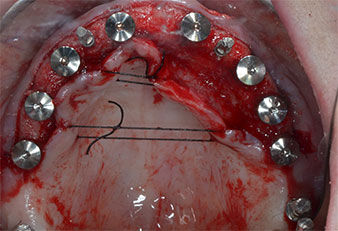

Tre anni dopo era il momento di una protesi dentaria mascellare dello stesso tipo. In base alla pianificazione con CBCT, il rialzo del seno mascellare è stato evitato con l'ausilio di impianti corti e una dima chirurgica è stata utilizzata per trasferire le posizioni pianificate alla cresta alveolare (Figg. 1 e 2).

Uno strumento piezoelettrico (Piezomed I1) a forma di fiamma, rivestito in diamante, è stato usato per contrassegnare le posizioni dell'impianto e per eseguire una preparazione pilota (Fig. 3). Si è prestato attenzione a utilizzare un movimento verticale ascendente e discendente, con potenza ridotta, irrigazione completa e bassa pressione (inferiore a 300 g). Successivamente è stato applicato uno strumento pilota (Piezomed I2A/I2P) per l'ingrandimento iniziale delle sedi dell'impianto del diametro di 2 mm (Fig. 4), seguito da un inserto da 3 mm (Fig. 5).